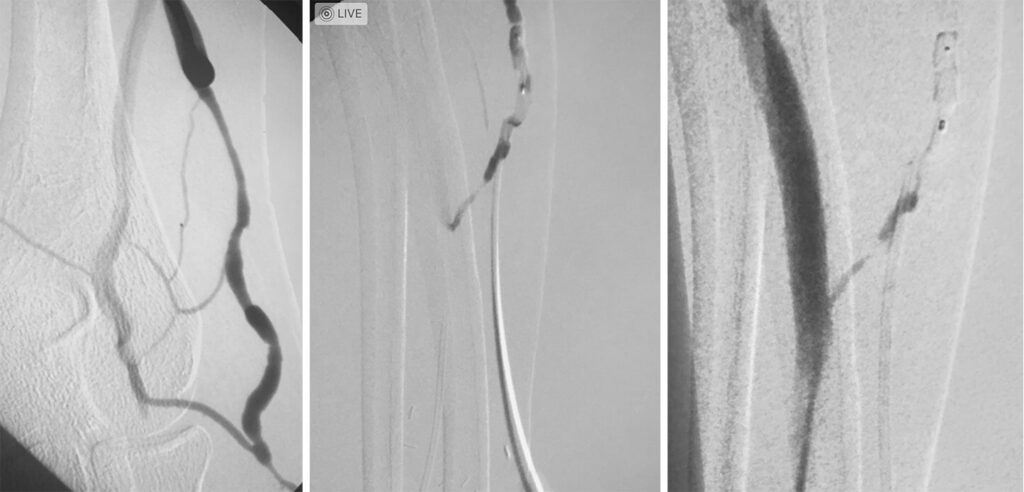

Case of the week: 70 year old patient with severe right leg pain with walking. Angiogram shows complete occlusion of the right superficial femoral artery. We were able to cross the occlusion with catheter and reconstruct the artery with balloon angioplasty and stents! All done without the need for open surgery!

Case of the week: Diaylsis patient with decrease in functioning of AV fistula - competing accessory vein needs to be shut down to fully route flow to AV fistula

Plug embolization of a competing vein for a successful maturation of the left arm AV fistula.

(*closing off of larger vein that takes blood away from a normal AV fistula)

Photo 1 - Accessory vein to shut down

Photo 2- Plug insertion into competing accessory vein

Photo 3- Full functioning AV fistula due to plug embolization